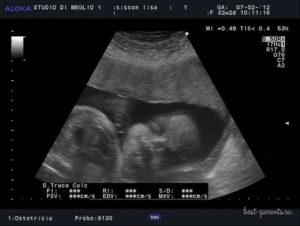

Узи на 38 неделе беременности норма

Ультразвуковое исследованиепроводится на 38 неделе строго понаправлению врача.

Обычно гинеколог спомощью данного методапытается прояснить конкретные вопросы:какова степень зрелости плаценты,имеется ли кислородное голодание илиобвитие пуповиной, каково состояние иколичество амниотической жидкости.

Взависимости от полученных на УЗИрезультатов врач дает свое заключениео состоянии здоровья мамы и ребенка, атакже рекомендации по выбору вариантародоразрешения.

При УЗИ на 38 неделе беременности норма развития плода определяется с помощью измерений всех важнейших показателей. Хотя дети на этом сроке отличаются друг от друга размерами, все же есть вариации нормы, от которых отталкиваются специалисты при оценке развития младенца.

Размеры ребенка в 38 недель уже не определяют срок беременности, они больше зависят от генетических факторов и от того, как питается будущая мама. В среднем его вес составляет 2900-3100 г, а рост от темени до копчика 35 см. Окружность головы и грудной клетки у плода примерно равны.